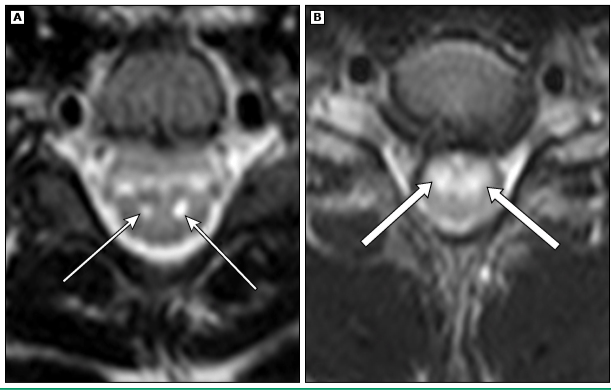

The primary spinal cord MRI abnormality is:

Hyperintensity of the central gray matter.